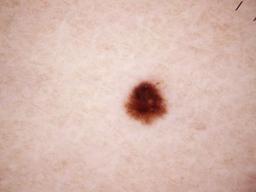

{

"age_approx": 50,

"anatom_site_general": "lower extremity",

"concomitant_biopsy": false,

"diagnosis_1": "Benign",

"diagnosis_2": "Benign melanocytic proliferations",

"diagnosis_3": "Nevus",

"diagnosis_confirm_type": "serial imaging showing no change",

"image_type": "dermoscopic",

"lesion_id": "IL_4096324",

"melanocytic": true,

"sex": "female"